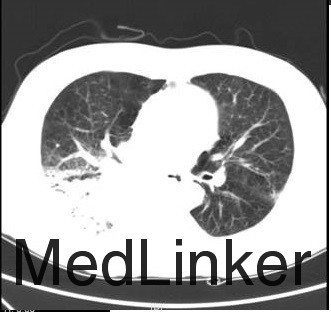

入院情况:入院查体:体温:36.0℃,脉搏:87次/分,呼吸:18次/分,血压:140/78mmHg。发育正常,营养良好,急性面容,表情痛苦,被动体位,神志清楚,精神状态较差,查体合作。呼吸规整,左肺呼吸音粗,右侧中下肺呼吸音减低,左侧肺底未闻及湿性罗音,无胸膜摩擦音。心前区无隆起,心尖搏动未见异常,心浊音界未见异常,心率87次/分,律齐,各瓣膜听诊区未闻及病理性杂音,无心包摩擦音。腹平坦,无腹壁静脉曲张,腹部柔软,无压痛、反跳痛,腹部无包块。肝脏肋下未触及,脾脏肋下未触及,Murphy氏征阴性,肾区无叩击痛,有移动性浊音阳性。 广州医学院一附院:头颅MRI平扫+增强:双侧额叶、半卵圆中心、放射冠多发缺血灶,侧脑室外周脑白质脱髓鞘改变,头颅MRI未见明确转移灶。胸部+上腹部增强CT:右下肺背段肿物,考虑肺癌可能性大,并右肺门淋巴结转移,右下肺阻塞性炎症,肝S5-S7段多发稍低密度结节,考虑转移可能性大。 2015-10-26 血常规乙+CRP:CRP<5.0mg/L;WBC9.910E9/L;NEU8.4810E9/L;LYM0.7510E9/L;NEU%85.6%;LYM%7.6%;RBC3.4910E12/L;HGB115G/L;HCT34.7%;PLT12910E9/L;2015-10-26 血气组合(乳酸):pH7.42;pCO245.5mmHg;pO275mmHg;Na142mmol/L;K3.6mmol/L;Lac5mmol/L;HCO3-(P)29.1mmol/L;ABE4.5mmol/L;sO295%;2015-10-26 凝血四项+血浆D-二聚体(免疫学方法):PT15.48秒;Fib1.27g/L;D-Dimer14500ug/L。2015-10-27 B型钠尿肽前体(PRO-BNP)测定+嘉禾心肌酶组+血清肌钙蛋白Ⅰ(cTnI;免疫学方法):CK-MB5μg/L;cTnI<0.010μg/L;PRO-BNP<70ng/L;AST115U/L;CK344U/L;LDH4583U/L;2015-10-27 凝血四项+血浆D-二聚体(免疫学方法):PT14.66秒;PTA80%;INR1.15;TT17.3秒;APTT33秒;Fib2.12g/L;D-Dimer5670ug/L;2015-10-27 肝功一组:T Bili31.48umol/L;D Bili13.94umol/L;I Bili17.54计算值;T PROT60g/L;ALB36g/L;GLB24.00g/L;ALT74U/L;AST117U/L;ChE3.88KU/L;2015-10-27 血常规乙+CRP:CRP11.16mg/L;hsCRP>5.0mg/L;WBC10.2510E9/L;NEU8.1910E9/L;LYM0.9710E9/L;RBC4.0910E12/L;HGB132G/L;PLT13210E9/L;2015-10-27 血气组合(乳酸):pH7.47;pCO245.8mmHg;pO266mmHg;Na137mmol/L;K3.9mmol/L;Ca1.07mmol/L;Cl93mmol/L;Lac3mmol/L;HCO3-(P)33.1mmol/L;ABE8.5mmol/L;B超:双侧股动脉粥样硬化并多发斑块形成。余双下肢上述动脉、上述静脉未见异常。心内结构未见异常。CDFI心内未见异常血流。左室舒张功能减低。CT:对比2015-10-10CT:1、右肺下叶背段占位,考虑肺癌伴纵隔及右肺门淋巴结转移,病灶较前略增大;2、考虑右肺下叶阻塞性肺炎;3、考虑肺气肿、右侧少量胸腔积液。4、主动脉硬化。5、肝内弥漫斑片状及结节状低密度灶,考虑转移。